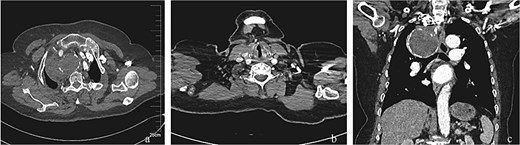

Considering the serious symptoms of chest pain and dyspnea, which indicated that the SAA might rupture at any time and could cause acute airway obstruction, emergency surgery was performed. The procedure was as follows (Fig. 2): Angiography was conducted immediately following a retrograde right femoral artery approach. The angiography showed a gourd-shaped calcification near the mediastinum in the upper lobe of the right lung, and the brachiocephalic trunk artery (BA) and the right common carotid artery (CCA) were well visualized. An SAA erupted from the right beginning of the right subclavian artery, and the aneurysm was gourd-shaped; the inflow artery was at the lower layer, and the outflow artery was at the upper layer. Based on these findings, we decided to place a covered stent through the BA and CCA. However, the diameter of the BA was 13 mm and the CCA was 8 mm. The normal covered stents were of equal diameter. Therefore, we decided to use a descending diameter covered stent, Endurant II LIMBS, which is commonly used in the endovascular treatment of abdominal aortic aneurysms. As the delivery length of the stent is only 57 cm, we could not place the stent through the femoral artery. The CCA was the suitable operative approach. The right CCA was dissected out, a retrograde puncture of the right CCA was performed, and a 14F introducer sheath was placed. A 16 mm–10 mm–93 mm Endurant II LIMBS (Medtronic Ireland, Parkmore Business Park West, Galway, Ireland) was implanted through the CCA approach. Immediately after the deployment of the stent grafts, angiography was performed, and no endoleak was observed. The right common carotid artery was sutured with a 6–0 Prolene suture. To assess the condition of the upper aneurysm, angiography was performed through the right brachial artery. The partial cavity of the aneurysm could be visualized, but the origins of the vertebral artery and internal thoracic artery were close to the aneurysm. Therefore, coil embolization of the outflow artery was performed. Considering that this side of the vertebral artery was not dominant, the origin of the right vertebral artery was not protected. Angiography was performed after embolization; no endoleak was found, the BA and the right CCA were well visualized, and the distal subclavian artery was visualized later through the collateral circulation.

Endovascular procedural steps. (a) Pre-interventional angiography identifies the SAA originating from the ostium of the right subclavian artery. (b) Fluoroscopic guidance demonstrates retrograde deployment of the tapered stent-graft through the common carotid artery approach, with real-time angiography confirming appropriate stent positioning. (c) Post-stent angiography reveals residual aneurysm cavity perfusion through persistent outflow tracts. (d) Selective embolization of the outflow artery using detachable coils (chevrons) achieves complete cavity obliteration. (e) Final control angiography documents technical success: Preserved patency of the brachiocephalic trunk and right common carotid artery, absence of endoleak, and delayed opacification of the distal subclavian artery via collateral circulation.